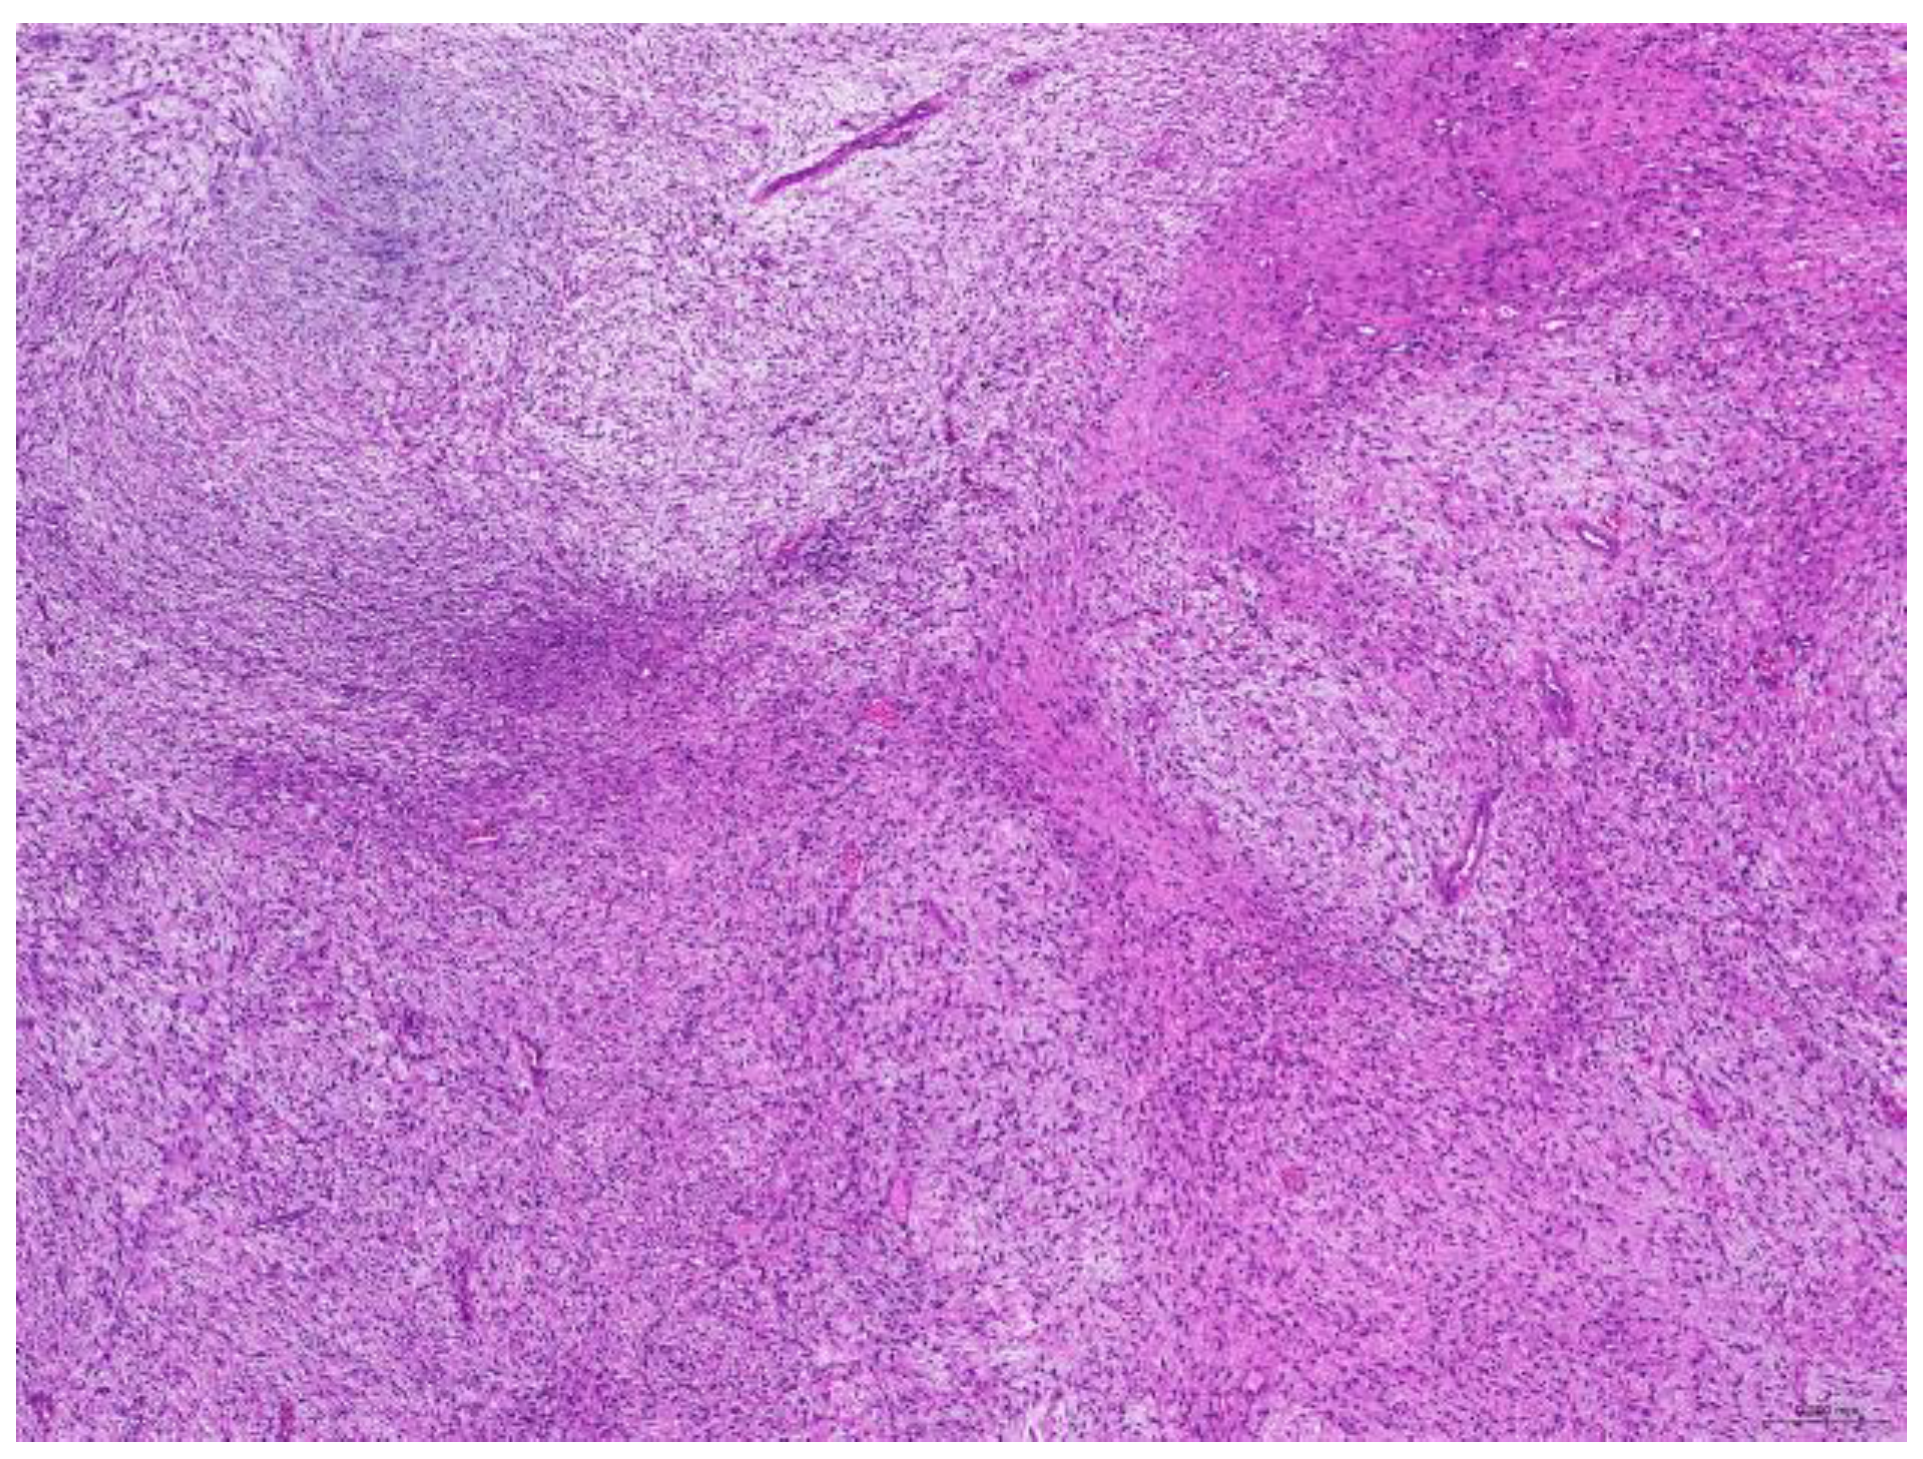

Of the 85 biopsy samples, the most commonly affected system was the integumentary system (48.2%, 41/85), followed by the reproductive system (42.4%, 36/85), the digestive system (8.2%, 7/85), and the urinary system (1.2%, 1/85) (Table 3). Of the 41 rabbits with an affected integumentary system, 39 had neoplastic and two had non-neoplastic disorders. The median age of these affected rabbits was 87 (12–149) months. There were 15 females and 26 males, with a female-to-male ratio of 0.54:1. The most common integumentary diagnosis was fibrosarcoma (29.3%, 12/41) (Figure 1), followed by trichoblastoma (19.5%, 8/41) (Figure 2), fibroma (9.8%, 4/41) (Figure 3), lipoma (7.3%, 3/41), mammary gland adenoma (7.3%, 3/41), and mammary gland adenocarcinoma (4.9%, 2/41) (Figure 4), among others. The median age of the rabbits with fibrosarcomas was 108 (54–126) months. Of the 12 cases with fibrosarcoma, 4 were females and 8 were males, with a female-to-male ratio of 0.5:1. The tumors were located on the neck, chest, abdomen, and extremities. The median age of the rabbits with fibromas was 101 (48–108) months. All four of these were males, with tumors exclusively located on the chest. Myxosarcoma was diagnosed in a 108-month-old male rabbit, with the tumor located on the left elbow (Figure 5).

Figure 1. Fibrosarcoma. The neoplasm is located in the dermis and is arranged in streams (scale bar = 200 µm). Hematoxylin and eosin staining.